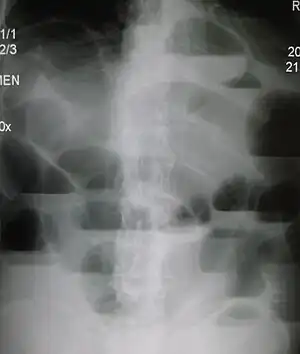

| Upright abdominal X-ray demonstrating a small bowel obstruction. Note multiple air fluid levels. | |

Radiological signs of bowel obstruction include bowel distension and the presence of multiple (more than six) gas-fluid levels on supine and erect abdominal radiographs. Ultrasounds may be as useful as CT scanning to make the diagnosis.[13]

Most people with SBO are initially managed conservatively because in many cases, the bowel will open up. Some adhesions loosen up and the obstruction resolves. The patient is examined several times a day, and X-ray images are made to ensure he or she is not getting clinically worse.[24]